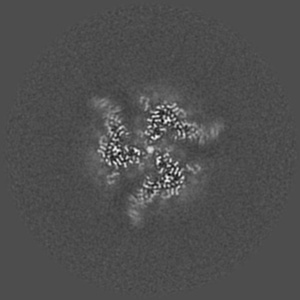

HIV-1 Env (BG505 SOSIP.664) in complex with the IgA bNAb 7-269 and the antibody 3BNC117.

Single-particle2.8 Å

Sample: Ternary complex of HIV Env (BG505 SOSIP.664) with bNAbs 3BNC117 (IgG Fab) and 7269 (IgA Fab)